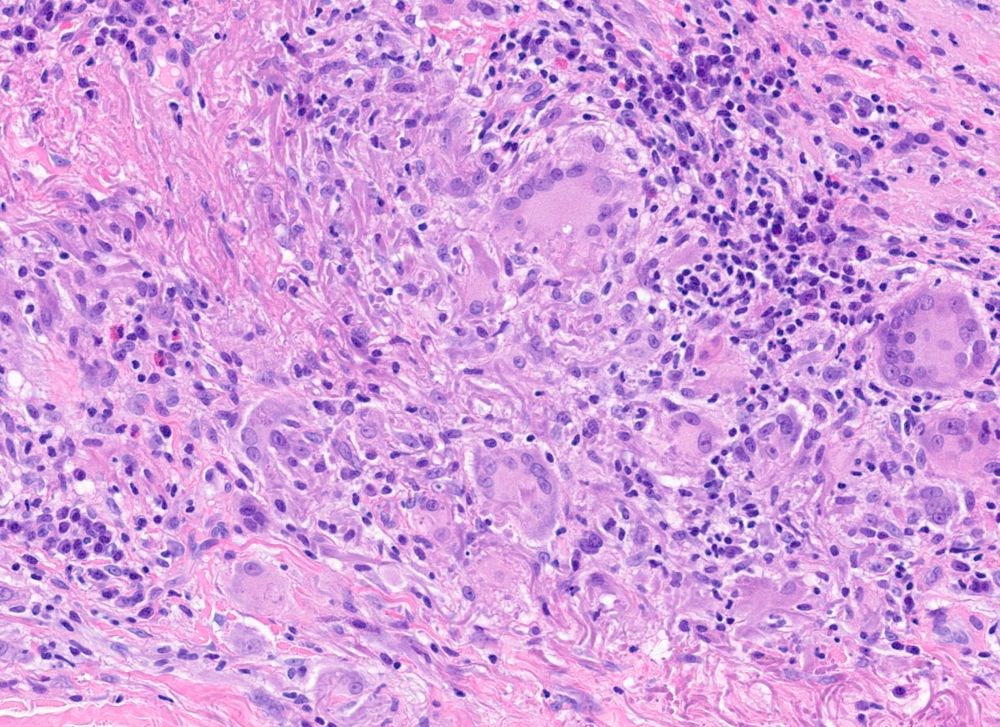

It’s an actinic granuloma sort of evening. The giant cells are enjoying their supper 🤣 #PathSky #dermpath

November 18, 2024 at 9:24 PM